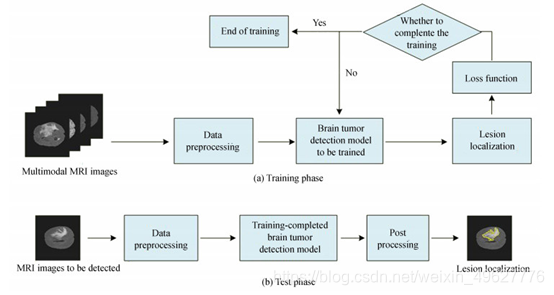

实现脑部MRI影像中的肿瘤病灶区域的检测,采用端到端的网络进行训练和测试.脑肿瘤检测网络整体分为两个阶段:训练阶段和测试阶段.多模态融合脑肿瘤检测流程如图 1所示:

图 1 多模态融合脑肿瘤检测流程

在训练阶段中,首先将多模态的MRI脑肿瘤影像进行融合作为训练数据,并对训练数据进行预处理,然后送入到构建的脑肿瘤检测模型中进行训练,根据模型输出的病灶定位结果与金标准计算误差值loss,如果误差值满足预先设置的条件则停止训练,否则继续训练网络.在训练阶段中,将待检测的样本进行预处理,送入到训练完成的脑肿瘤检测模型中进行检测,并对检测结果进行后处理,最后输出脑肿瘤的病灶定位结果.